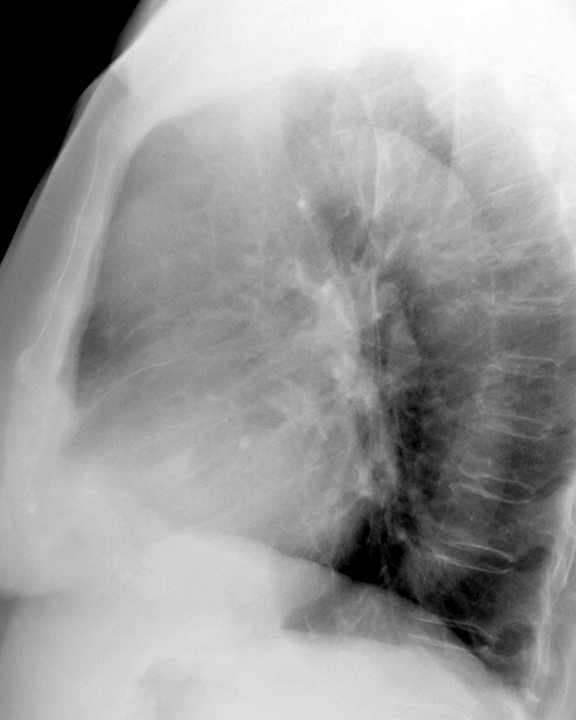

Case 8b Thymoma Lat